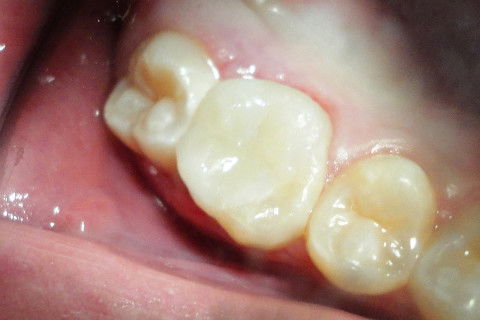

Aspecto Clínico Inicial